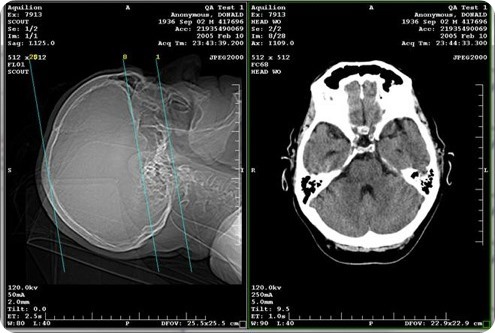

The most common method of image sharing over the past decade has been compact discs (CDs). Physicians place exams and reports on CDs and give them to patients to take to their medical appointments for treatment or second opinions; however approximately 20 percent of these CDs contain corrupt or bad files.

Frequent loss is another CD problem, particularly for critically ill patients being transported in ambulances with small discs tucked into their personal belongings.

When a CD is unreadable or lost, a patient is usually re-scanned, which exposes the individual to added radiation and delays treatment. In fact, there are more than 600 million exams done each year in the U.S. and 10 to 20 percent of those are duplicate exams - totaling $10 billion in excess.